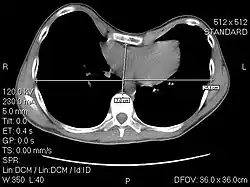

Auf klinischen Auswerteworkstations und CT-Bildern wird der Begriff „Zentrum“ meist mit „c“ (englisch center) und der Begriff „Breite“ meist mit „w“ (englisch width) abgekürzt. Statt „c“ wird bisweilen auch „l“ (englisch level) geschrieben.

Für die Beurteilung der Lunge wird ein Ausschnitt aus der Hounsfield-Skala gewählt, der die Dichtewerte der Luft in der Lunge und des Lungengewebes umfasst. Der niedrigste Dichtewert dieses Ausschnitts wird dem 'Grauwert' Schwarz, der höchste dem Wert Weiß zugeordnet. Alle Dichtewerte dazwischen bekommen linear die Grauwerte zwischen Schwarz und Weiß zugewiesen. Ein Lungenfenster mit Zentrum bei -600 HE und einer Breite von 1600 HE reicht also von -1400 HE bis 200 HE. Dichtebereiche kleiner -1400 werden gleichbleibend schwarz, die oberhalb 200 gleichbleibend weiß dargestellt.